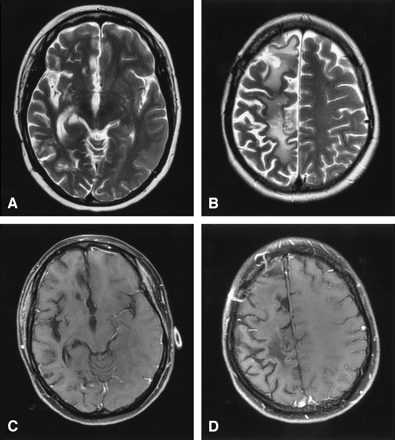

Lymphatic vasculitis, MR imaging post-treatment.

A and B, Axial T2-weighted images 5 months after therapy show resolution of edema and mass effect with residual foci of gliosis and extensive atrophy of the right cerebral hemisphere.

C and D, Axial T1-weighted postgadolinium images with fat saturation demonstrate interval resolution of the previously seen enhancing masses. Craniotomy defect is evident in the right frontal region from the previous biopsy.